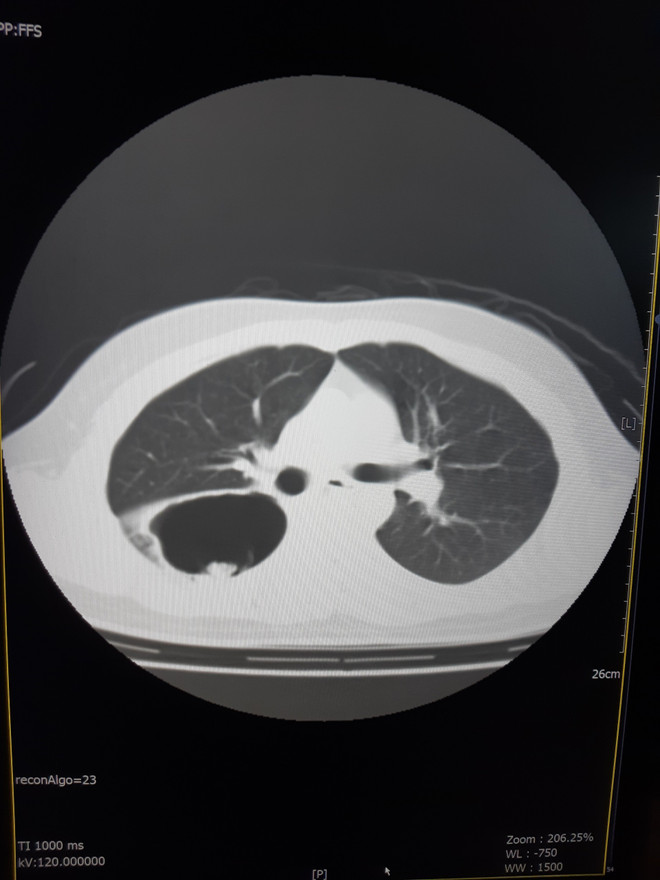

Ngày 3/11, Bệnh nhân T. được chuyển viện đến Bệnh viện C Đà Nẵng. Tại đây, bệnh nhân được các y, bác sỹ khám sàng lọc, chụp CT-scan lồng ngực, xét nghiệm cơ bản, đo chức năng hô hấp, tập phục hồi chức năng phổi, nâng cao thể trạng và được chẩn đoán bị hang nấm ở thùy trên và thùy dưới phổi phải.

Bệnh viện C Đà Nẵng phẫu thuật thành công ca bệnh u nấm phổi phức tạp ảnh 2Hình ảnh chụp X quang phổi bệnh nhân. (Ảnh: Văn Dũng/TTXVN)